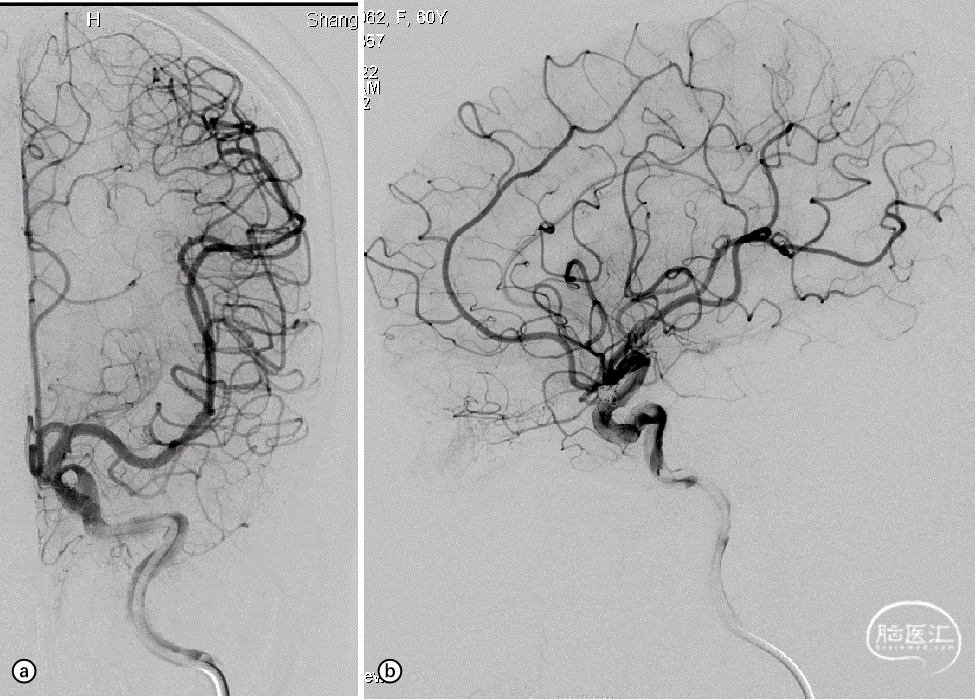

图7. a,b:术后即刻正侧位造影显示动脉瘤已完全闭塞(Raymond I级)。

患者术后3天出院,mRS 0分。